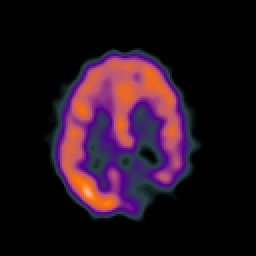

SPECT TC Study #7 -- Slice #37

[Home][Help][Clinical][Tour 1][Tour 2][Tour 3] Slice 37